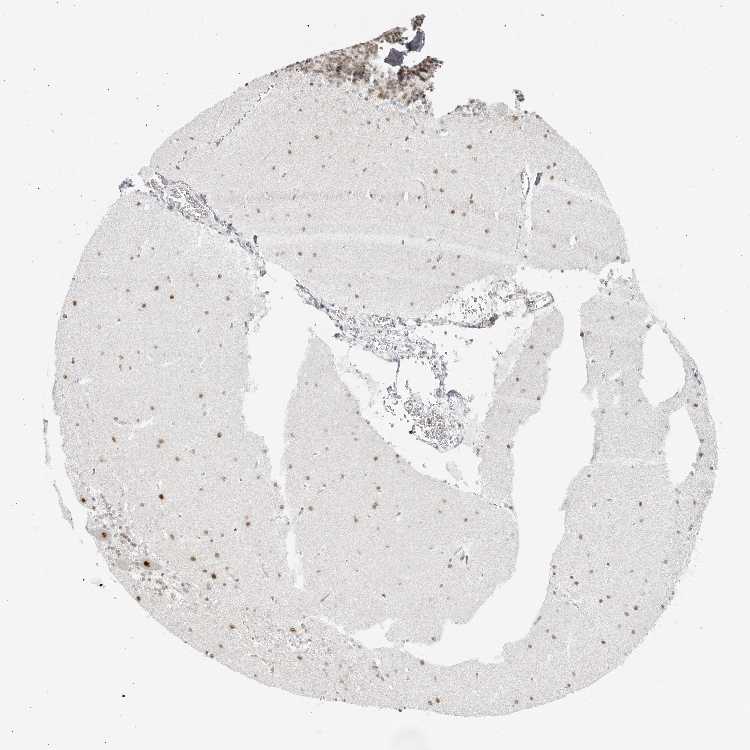

CEREBELLUM - Antibody stainingi

Antibody staining in the annotated cell types in the current human tissue is reported as not detected, low, medium, or high, based on conventional immunohistochemistry profiling in selected tissues. This score is based on the combination of the staining intensity and fraction of stained cells.

Each image is clickable and will lead to virtual microscopy that enables deeper exploration of all samples and also displays staining intensity scores, fraction scores and subcellular localization as well as patient and tissue information for each sample.

Antibody HPA027523

Purkinje cells High

Cells in granular layer Low

Cells in molecular layer High